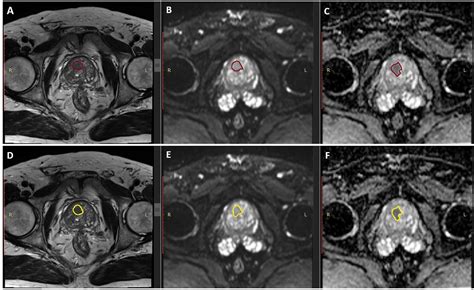

Discover how an MRI of the prostate provides high-resolution imaging for the accurate detection and diagnosis of prostate cancer. Learn how this non-invasive scan uses multiparametric techniques to identify suspicious lesions, improve biopsy precision, and guide personalized treatment plans for better patient outcomes. Explore the essential role of prostate imaging in modern urological care and early disease management.